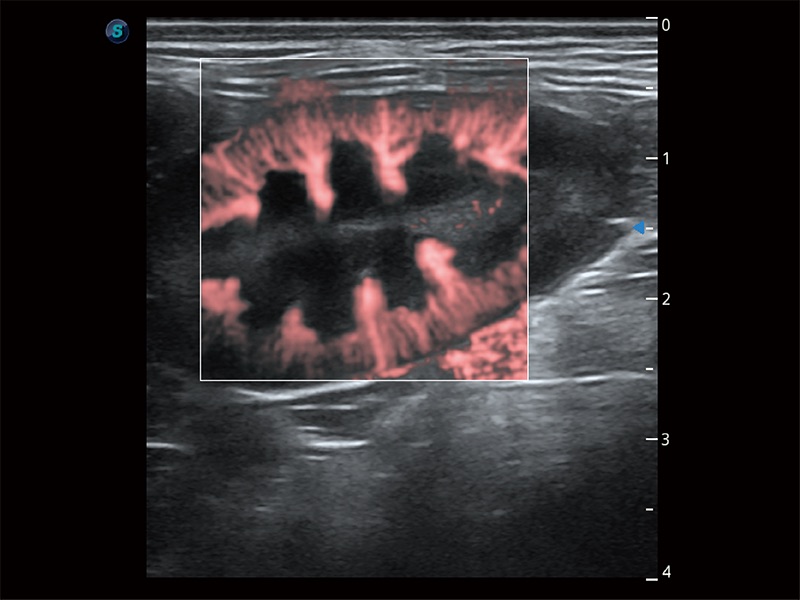

(犬)肠道

(犬)肾脏显微血流